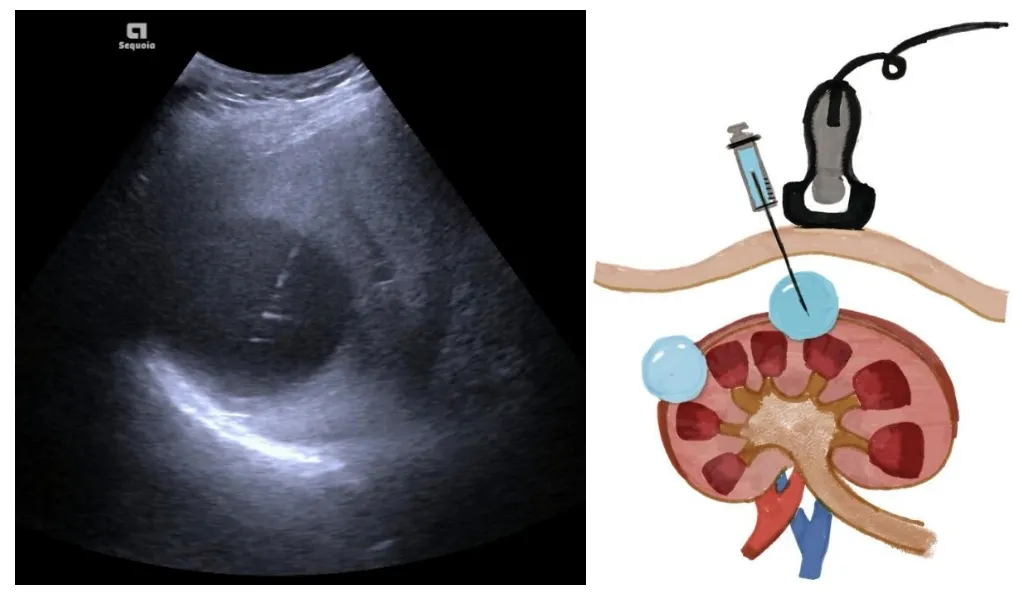

这不,今天就来给大家介绍一种堪称“囊肿克星”的治疗手段——超声引导下经皮穿刺硬化治疗。

这是一种什么样的治疗方法呢?

超声这个神奇的“GPS导航”,能精准定位囊肿的位置。在它的引导下,穿刺针如同被赋予了智慧,准确抵达囊肿部位。接着,医生会将囊肿内的液体缓缓抽出,随后注入硬化剂,让囊肿逐渐萎缩直至消失。

相比传统手术,这种治疗方式优势显著。它以针代刀,极大地减轻了患者的创伤,恢复速度也更快,治疗过程几乎感觉不到痛苦;而且,这种操作安全性极高,并发症少,让你可以放心接受治疗。

最重要的是,疗效确切,经过治疗后,囊肿明显缩小甚至消失,帮你轻松重拾健康生活。